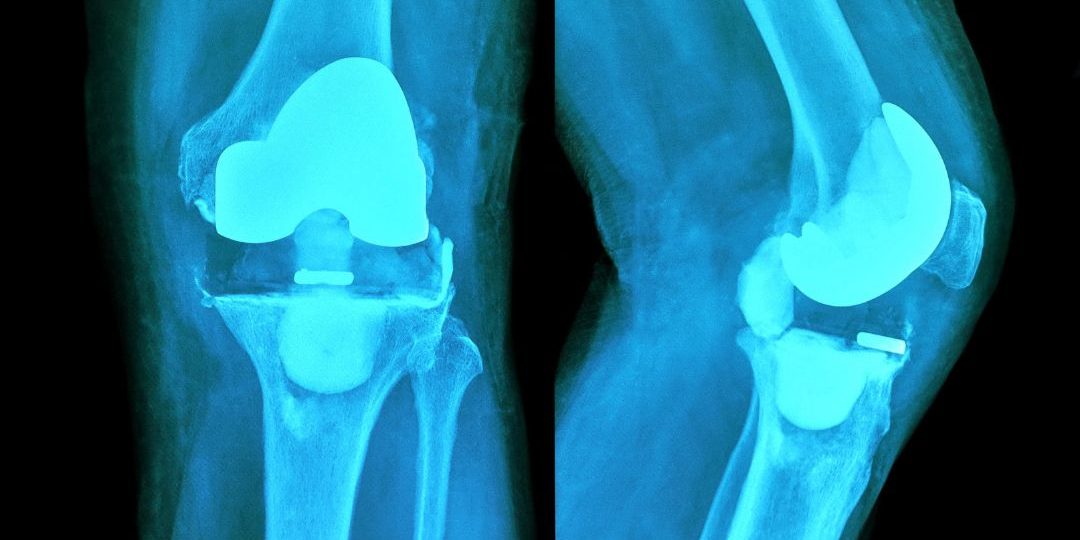

W pierwszej kolejności usuwana jest rzepka oraz przecinane są końce kości udowej i piszczelowej w celu dopasowania protezy do przestrzeni stawowej.

Obie części protezy są następnie mocowane do różnych kości za pomocą cementu lub śrub.

→ Całkowite, gdy staw jest całkowicie wymieniony. Należą do nich:

- Protezy zastępujące powierzchnie stawowe, w których usuwa się uszkodzony staw.

- Protezy z połączonymi komponentami, które zapewniają dużą stabilność dzięki połączeniu kości piszczelowej i udowej. Umożliwiają one obrót, zgięcie i wyprost.

- Oraz protezy samostabilne, w których uszkodzona powierzchnia jest zastępowana, a dzięki swojej konstrukcji zapewniają stabilność i funkcjonalność.

→ Z drugiej strony, istnieją protezy jednoprzedziałowe. Są one stosowane w przypadku ograniczonych zmian chorobowych w obrębie stawu.